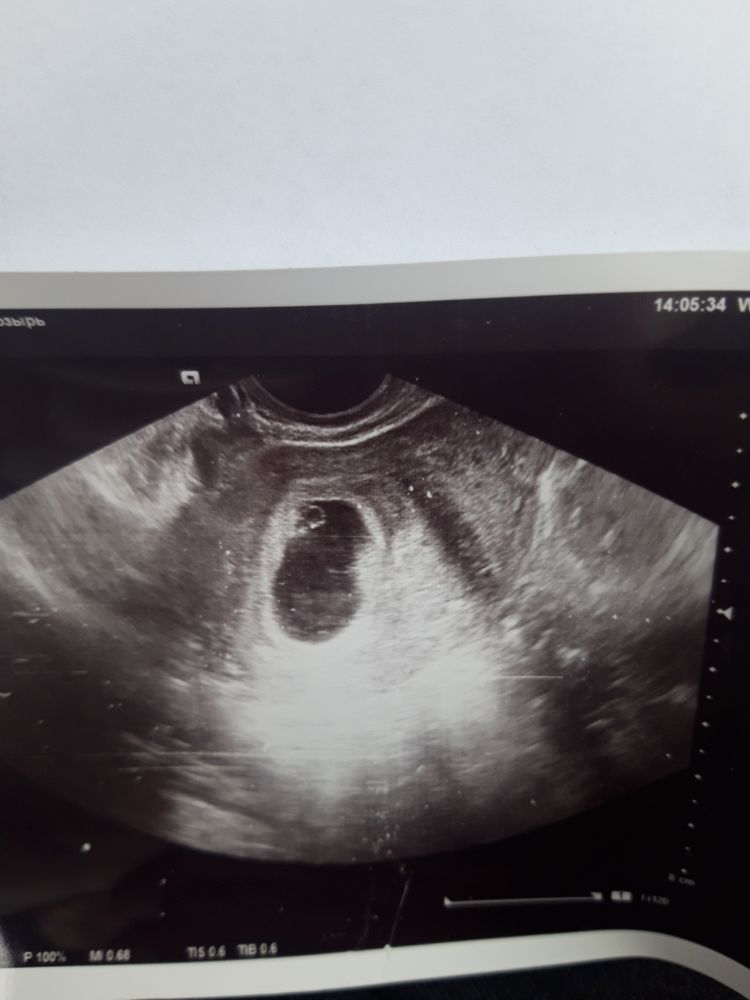

Узи 21дпп при хгч 24000

Сходила на узи, увидели плодный мешок 25мм, желточный мешок 2,5мм и это при хгч 24000. Поэтому видно уровень хгч не показатель, эмбриона пока нет. Но врач сказала, что если есть желточный мешочек, то и эмбрион точно появится, так ли это?